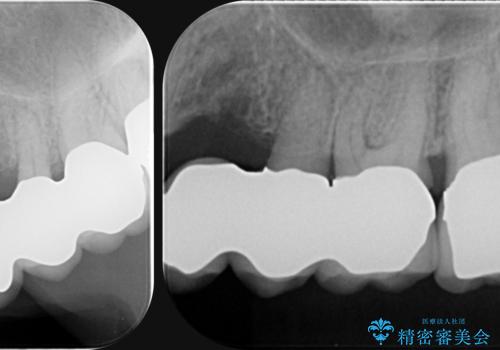

歯列不正による第一小臼歯の骨吸収が認められ、機能咬合力の回復、大きな側方力に連結することで抵抗することのできるブリッジ補綴を選択しました。

- 32万円(仮歯・フルジルコニアクラウン×4)費用は治療当時の料金となります

歯周病による深いポケット・大きな側方力・短い臨床歯根・欠損の補綴、これらの問題を解決するために歯周補綴を兼ねたブリッジを選択しました。